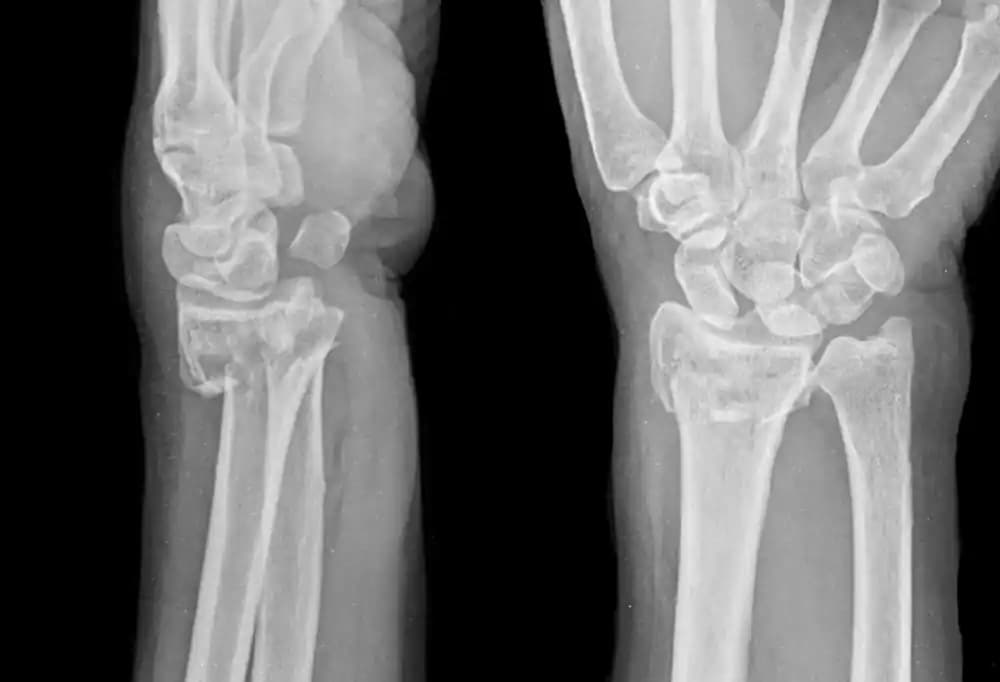

Radius kırığı tespiti için fiziki muayene ve röntgen çekimi yapılır. Röntgen çekiminde görülemeyen minimal derecedeki kırıklarda hastalanın kolu atele alınarak tedavi yöntemine başlanır. Atel ile tedavi yönteminde hastalardan kollarını çok fazla yormamaları ve oynatmamaları istenir. Atel ile tedavi yönteminde, minimal derecedeki kırıklar için tahmini iyileşme süresi 3 haftadır.

Ameliyat kararı, sıklıkla ikinci ve üçüncü tip Radius kırıklarında alınmaktadır. İleri derecedeki Radius kırıkları, röntgen ile görüntülenebildiği için tanı koymak ve ameliyat kararı almak daha kolay olmaktadır. Özellikle üçüncü tip kırıklar, çok parçalı kırıklar olduğundan ve kırık ile birlikte bağ dokusunun da zedelenmiş olmasından dolayı, ameliyat sırasında kırıklara ve bağ dokularına aynı anda müdahale edilir. Radius kemik başında oluşan ciddi kırıklarda protez kullanılarak bir ameliyat gerçekleşmesi mümkündür.